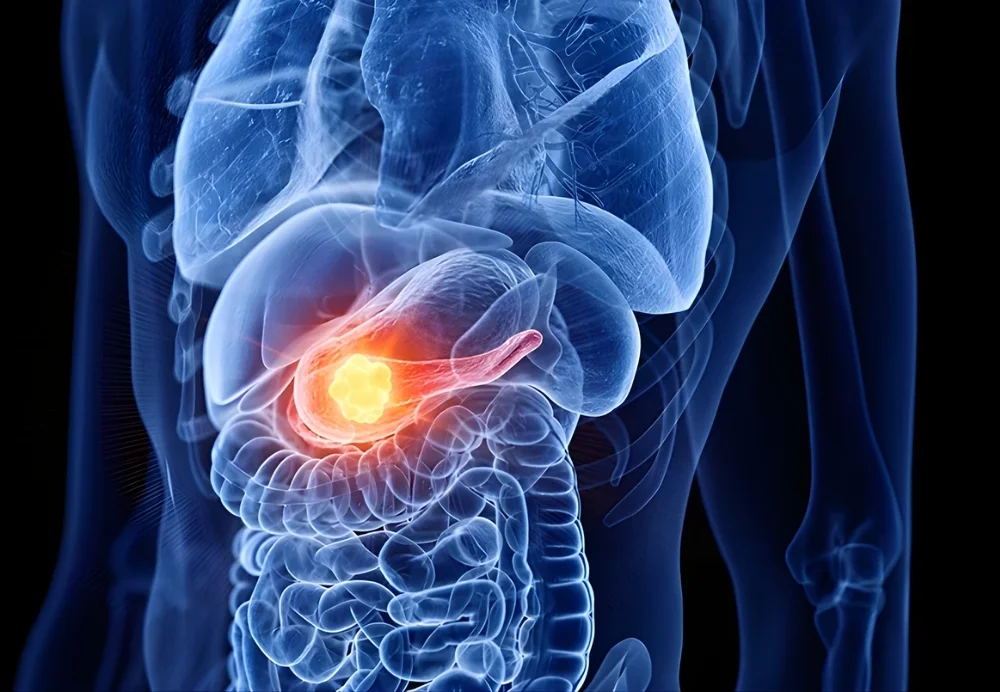

Pancreas cancer arises when abnormal cells in the pancreas grow uncontrollably, affecting its ability to produce digestive enzymes and hormones like insulin. Early symptoms may be subtle, but as the disease progresses, tumors can obstruct bile ducts, affect blood sugar levels, or invade nearby organs. Under the care of Dr. Anuj, pancreas cancer surgery is planned based on tumor type, stage, and patient health. The goal is complete cancer removal while maintaining pancreatic function and improving overall quality of life.

WHAT IS PANCREAS CANCER?

Pancreas cancer is a malignancy that develops when cells in the pancreas begin to grow uncontrollably. Most commonly, it starts in the exocrine cells, which produce digestive enzymes.

Over time, the tumor can invade surrounding structures, involve lymph nodes, and, if untreated, spread to the liver, lungs, or peritoneum. Early detection is key to improving outcomes, as pancreas cancer is often diagnosed at advanced stages due to subtle initial symptoms.